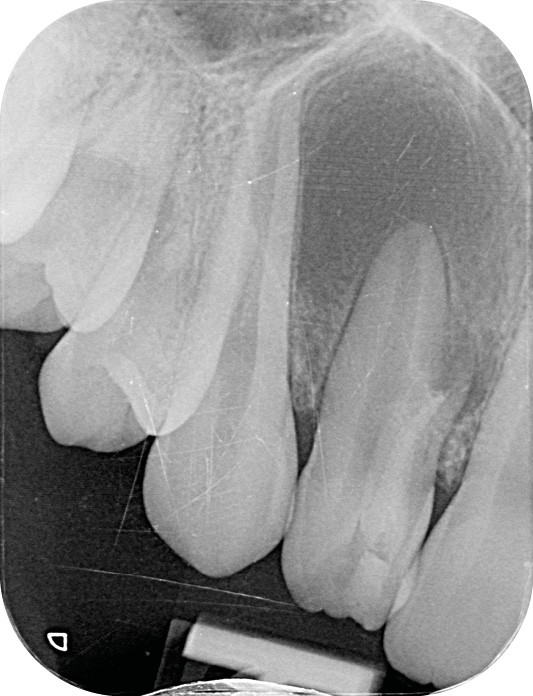

La patiente, âgée de 12 ans, s’est présentée à ma consultation avec une demande du chirurgien de réaliser le traitement endodontique de la 12 avant le curetage sous anesthésie générale. La radiographie périapicale préopératoire a mis en évidence une anatomie complexe. Les tests préopératoires ont montré un sondage parodontal sain, une percussion positive et un test au froid positif. La patiente présentait également une fistule vestibulaire active. Le Cone Beam a mis en évidence la présence d’une dens in dente et d’une lésion imposante ainsi qu’une palatoversion importante de la racine de la 12. La lésion est-elle responsable de ce mouvement dentaire ? (fig. 1, 2 et 3).

Le test au froid et la position de la lésion m’ont permis de prendre ma décision thérapeutique. En effet, la lésion située uniquement sur la face vestibulaire de la dent en regard de l’apex du canal de la dens in dente et la persistance d’un test au froid positif à travers chacune des séances de soins m’ont permis de m’assurer que la dent principale était bel et bien vivante.